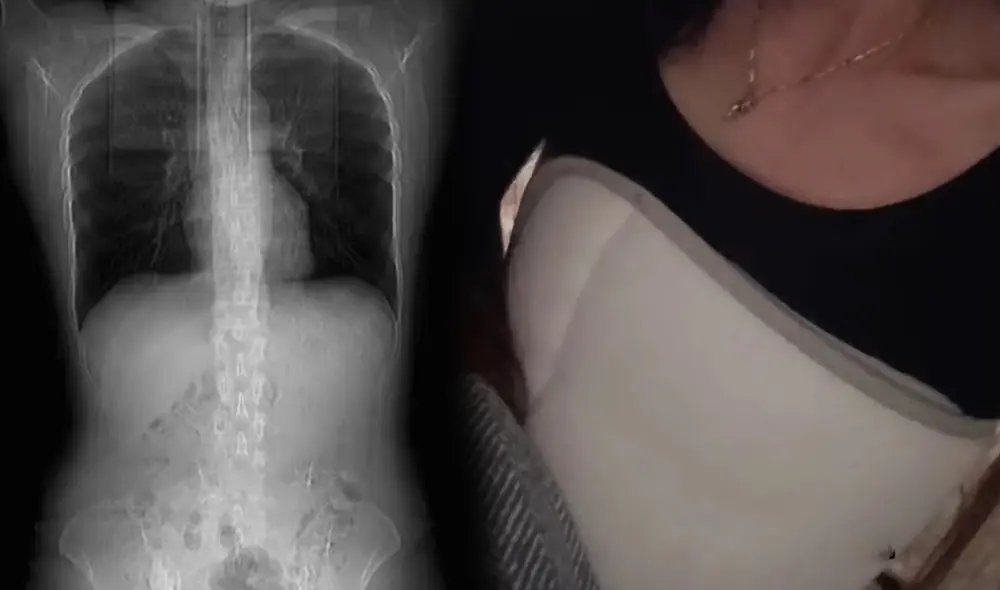

Ante estos síntomas, la mujer acudió a un centro médico donde se le realizó una tomografía, la cual mostró que los dolores se debían a que tenía cuatro de sus costillas rotas. Con este diagnóstico tuvo que ser vendada y deberá de permanecer en reposo cerca de un mes.

Asimismo, el médico señaló que este incidente se habría originado debido al bajo peso que la joven mujer presentaba. “Sus costillas se pueden ver claramente debajo de su piel. No hay músculo para sostener el hueso, por lo que es fácil que sus costillas se fracturen al toser”, indicó el profesional.